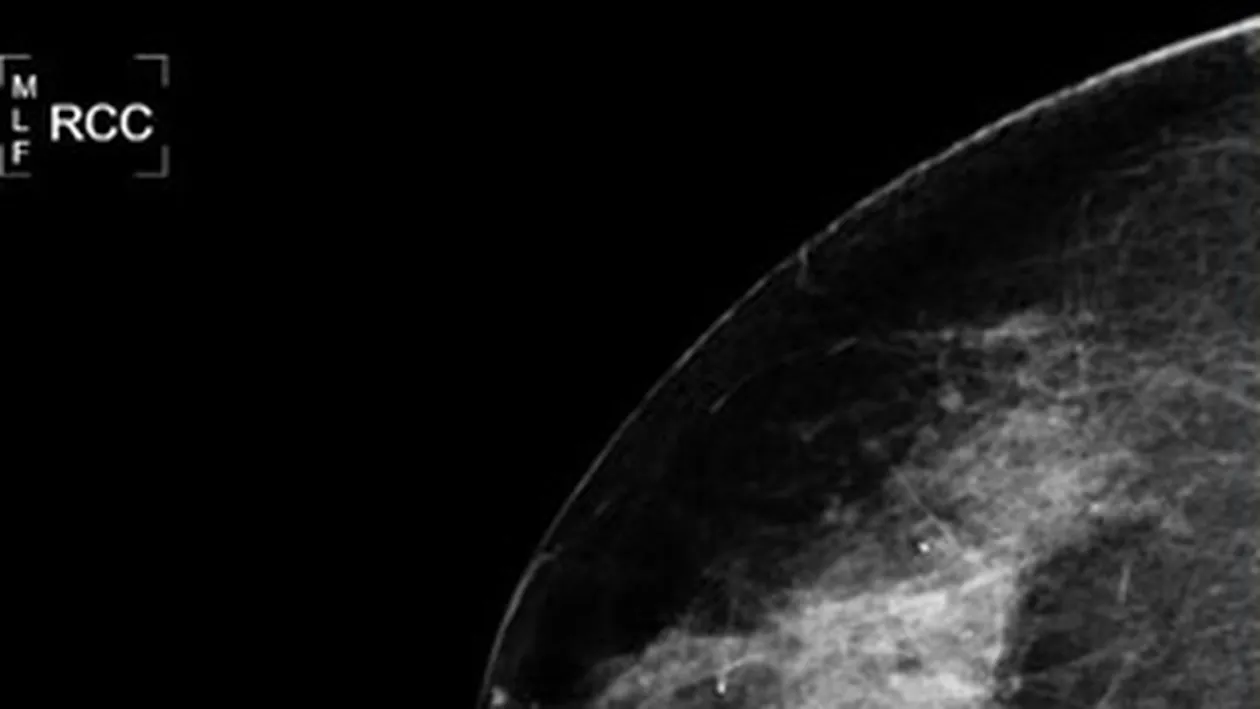

Mamografie realizata intr-un cabinet medical

NASA vrea sa dovedeasca utilitatea tehnologiei pe care o are la dispozitie, ajutand medicii sa descopere cancerul in stadiu incipient, prin efectuarea unor mamografii performante.

Programul spatial americanfoloseste un soft, numit MED-SEG, pentru a efectua mamografii al caror scop este descoperirea cancerului in stadiu incipient.

Doctorului Thomas Rutherford, directorul clinicii de ginecologie-oncologie a Universitatii Yale, crede ca folosirea acestei tehnologii poate reduce incidenta „erorii umane” in timpul diagnosticarii pe baza evaluarii ecografiilor si radiografiilor, permitand depistarea celulelor maligne in stadiu incipient.